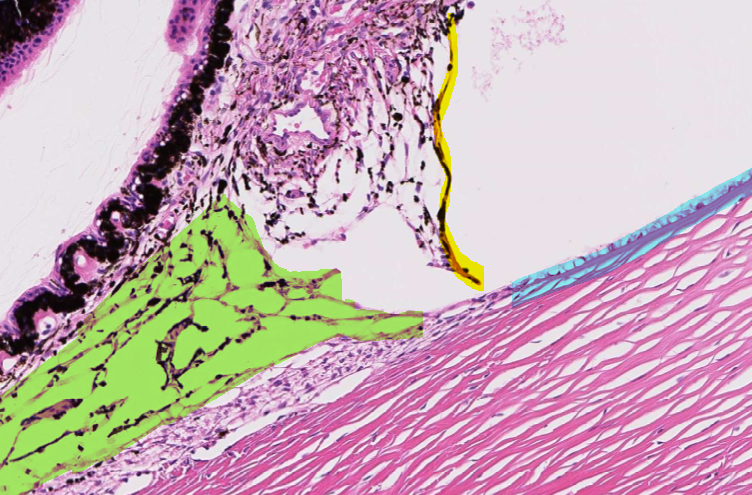

This is normal, healthy tissue of the eye.

What are the highlighted structures?

Green = ____

Yellow = ____

Blue = ____

A

Green = trabecular meshwork

Yellow = pectinate ligament

Blue = descemet’s membrane